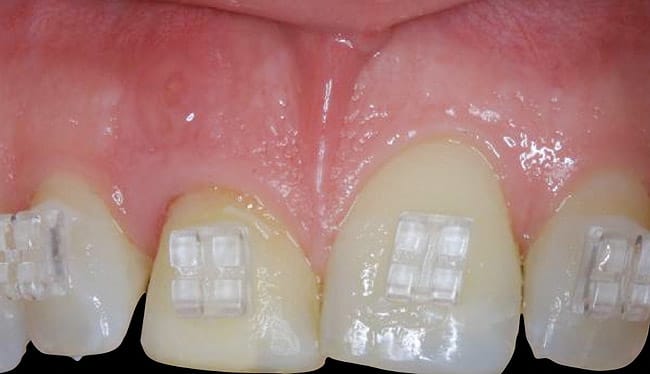

This was an esthetic high-risk case due to extremely high patient expectations and existing distal papilla bone loss. The patient, who had sustained a vertical root fracture of the right central incisor during a snowboarding accident, also presented with a facial fistula at mid-root level (Figure 4 and Figure 5).

The decision was made to use orthodontics to correct the occlusion and tooth position of the adjacent teeth. It was also decided to force erupt the hopeless lateral incisor and central incisor to improve the missing interproximal bone on the distal surface of the incisor. Forced eruption of the incisor also would move the fracture more coronal and create a healthy environment prior to implant placement. Treatment goals were to decrease inflammation and the fistula, overcompensate for recession, and improve osseous levels. The sinus tract progressively decreased as the tooth was force erupted (Figure 6). At the time of immediate placement, a CTG was also performed to preserve the facial ridge profile along with a custom healing abutment (Figure 7).